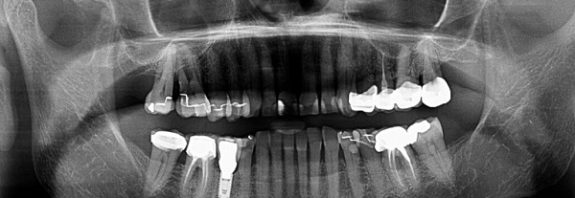

False teeth could double as hearing aids

False teeth could double as hearing aids Jawbones transmit sound just as well as the bone that traditional hearing aids … Continue reading False teeth could double as hearing aids